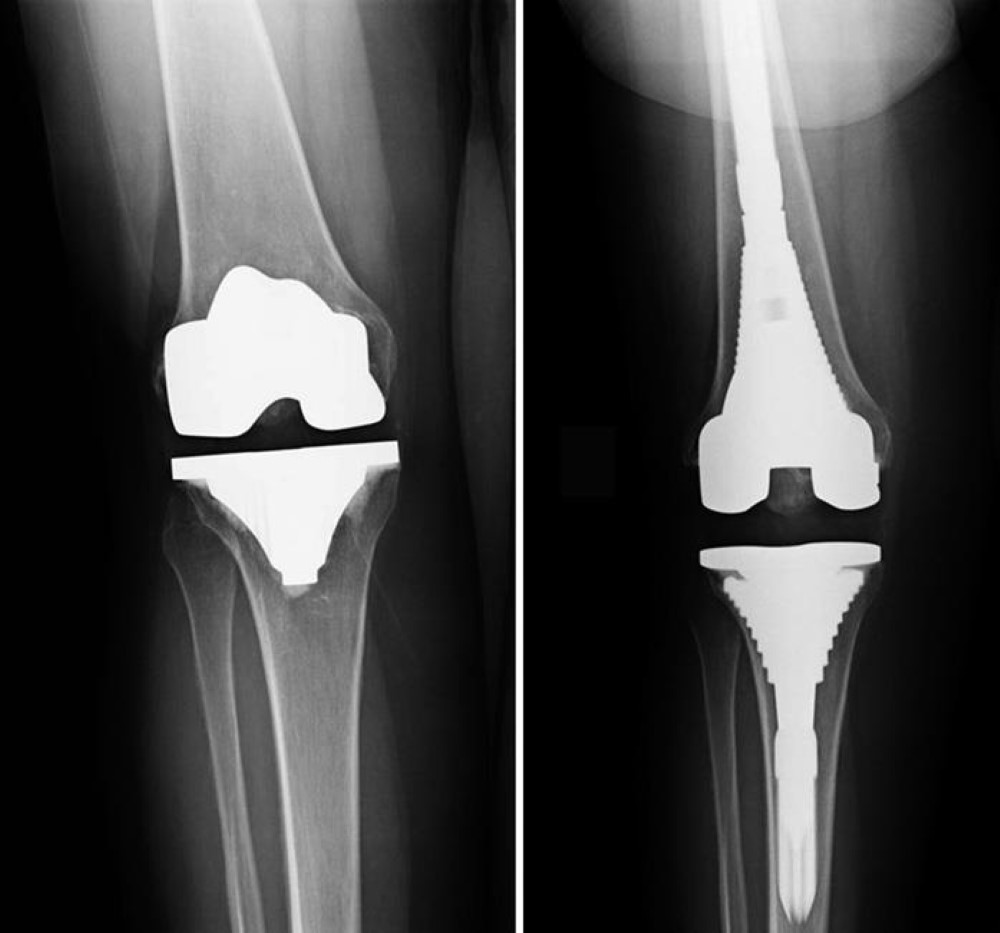

Revision knee replacement surgery involves replacing part or all of your previous knee prosthesis with a new prosthesis. Although total knee replacement surgery is successful, sometimes the procedure can fail due to various reasons and require a second revision surgery.

During total knee replacement, the damaged cartilage and bone is removed from the knee joint and replaced with artificial components. Artificial knee joints are usually made of metal, ceramic or plastic and consist of the femoral component and the tibial component.